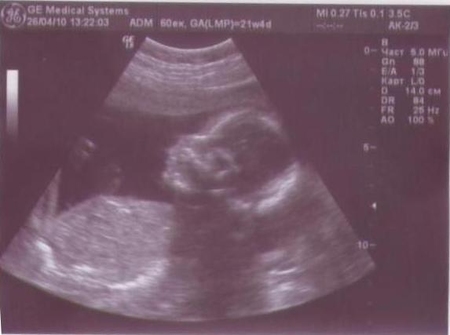

жду мальчика, 23 неделя

Молодцы!! совсем большие на картинке! Замечательный малыш!!!

классно - молодцы - так малыша хорошо видно)))) лапульки))) совсем большие уже)))

спасибо...наша первая фотка...папа её себе сразу в закладки забрал и в первый день где-то выронил,отругала его,хорошо хоть я сразу отсканировала... малой руку под голову на узи подкладывал,другой рукой нос себе гладил=)))

ой какой смпотишный сыночек(ттт не сглазить)!